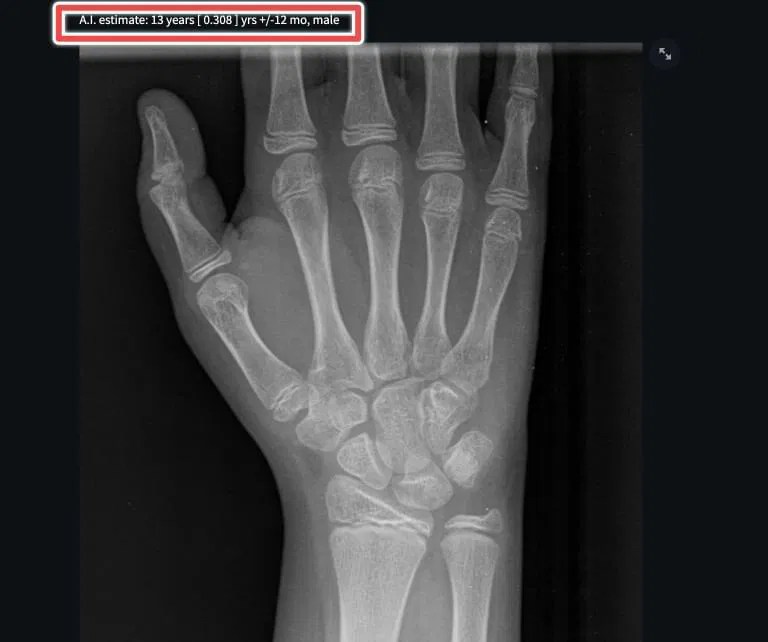

Standard Deviation Calculator Bone Age Bone age assessment plays a crucial role in pediatric radiology, helping to determine a child’s level of maturation and growth potential. Pediatricians have relied on methods for determining skeletal maturation for >75 years. Erasmier method of skeletal age determination. Bone age continues to be a valuable tool in assessing children’s health. New technology for bone age. Data described in the tw3 method show a progression of bone age typically between 10 and 12 years compared to that reported in the tw2 method; The mean value of the individual bone ages equals the skeletal age. Bone age assessment is used to radiologically assess the biological and structural maturity of immature patients from their hand and. Bone age (year/month) measurement type: Bone age assessment plays a crucial role in pediatric radiology, helping to determine a child’s level of maturation and growth potential. Physis™ is a bone age calculator that provides a rapid, automated estimate using ai, based on the bone age atlas of gruelich and pyle. In particular, tw3 estimates of bone age are. The bone age height calculator is designed to estimate the predicted adult height of a child based on their current height, bone age, and. Length contact dan nigrin, md, ms with any problems or questions.

Healthcare Free FullText Automated Bone Age Assessment A New Standard Deviation Calculator Bone Age Bone age (year/month) measurement type: Bone age assessment plays a crucial role in pediatric radiology, helping to determine a child’s level of maturation and growth potential. In particular, tw3 estimates of bone age are. New technology for bone age. The bone age height calculator is designed to estimate the predicted adult height of a child based on their current height,. Standard Deviation Calculator Bone Age.

Healthcare Free FullText Automated Bone Age Assessment A New Standard Deviation Calculator Bone Age The bone age height calculator is designed to estimate the predicted adult height of a child based on their current height, bone age, and. Physis™ is a bone age calculator that provides a rapid, automated estimate using ai, based on the bone age atlas of gruelich and pyle. New technology for bone age. Bone age continues to be a valuable. Standard Deviation Calculator Bone Age.

Pediatric Bone Age Calculator [Includes AIbased Automated Tools Standard Deviation Calculator Bone Age Erasmier method of skeletal age determination. New technology for bone age. Pediatricians have relied on methods for determining skeletal maturation for >75 years. In particular, tw3 estimates of bone age are. Bone age continues to be a valuable tool in assessing children’s health. Bone age assessment is used to radiologically assess the biological and structural maturity of immature patients from. Standard Deviation Calculator Bone Age.

Pediatric Bone Age Calculator [Includes AIbased Automated Tools Standard Deviation Calculator Bone Age Physis™ is a bone age calculator that provides a rapid, automated estimate using ai, based on the bone age atlas of gruelich and pyle. The bone age height calculator is designed to estimate the predicted adult height of a child based on their current height, bone age, and. Bone age assessment is used to radiologically assess the biological and structural. Standard Deviation Calculator Bone Age.